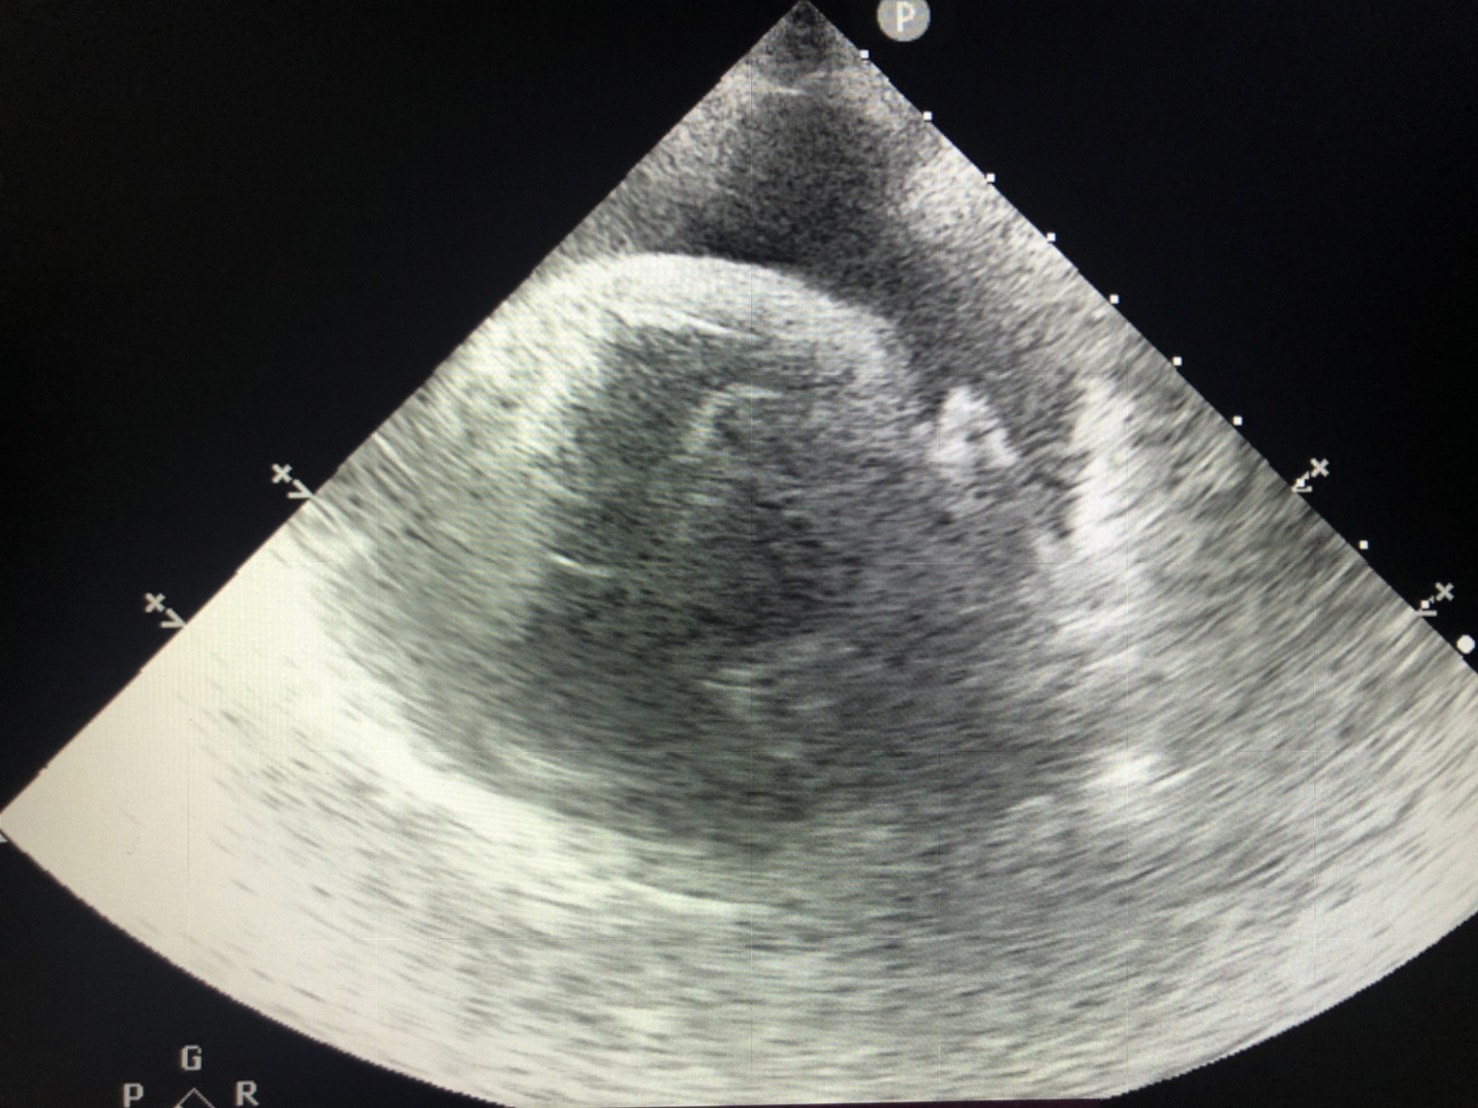

心臟的最外層有一層膜樣構造稱為心包膜,

心臟與膜之間會有少量組織液蓄積其中,達到潤滑的作用。

若是因為腫瘤、心臟疾病、發炎或其他狀況導致液體蓄積在心臟跟心包膜之間,

稱之為心包囊積液。

同樣地,產生心包囊積液時,心臟擴張會受限,無法將身體的血液回收至心房內,

因此通常會伴隨著腹水的產生,當壓迫到左心室造成心臟輸出量降低時,甚至可能低血壓而造成動物休克死亡。

若是已造成心包填塞的情況下,需抽取心包囊積液,緩解心臟因受到壓迫而造成的致命問題。

同時間需進行身體其他檢查如血液學檢查、X光、心臟超音波等……找到產生心包囊積液的原因。